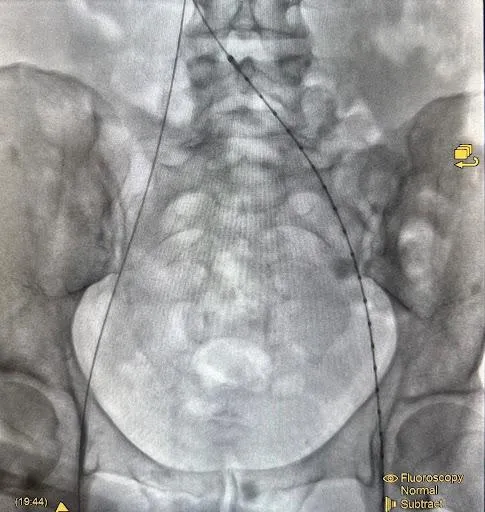

An imaging test that uses contrast dye and X-ray to clearly visualize the iliac vein, helping diagnose vascular conditions and assess blood flow.